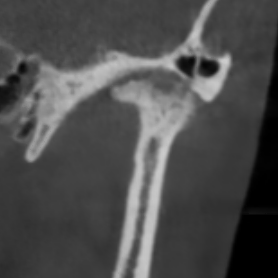

Перед началом лечения я провожу часовую первичную консультацию. Для этой встречи вам необходимо сделать «МРТ ВНЧС» и «КЛКТ двух челюстей с захватом ВНЧС в привычном прикусе».

Во время консультации мы смотрим и анализируем ваши исследования. Я подробно объясняю строение ВНЧС, показываю все причинные факторы вашей проблемы, отвечаю на все вопросы «Почему?»